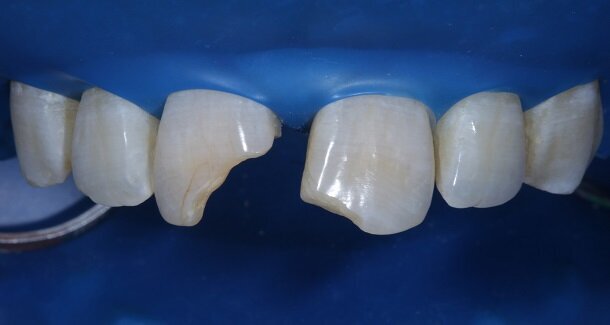

The figures show the clinical work flow involved. In the 1st appointment Oral prophylaxis, oral hygiene instructions were followed by an impression that was sent to the lab for a wax up [Fig 3 and 4]. In the subsequent appointments, Endodontic treatment was followed by Intra and extra coronal office bleaching using the Pola office bleaching kit. After two weeks, the shade stabilised post bleaching. Shade selection, rubber dam isolation and preparation was done on both the teeth to receive Direct composite veneers so as to close the midline diastema as well as correct the fractured teeth and the slight mal-alignment. Controlled Body Thickness (CBT) technique of layering was used with 3M Z350XT shades - Dentin shades A3, A2 and Enamel shades A2, clear translucent [Figures 5 to 11]. This was followed by the Finishing and polishing protocol as described in the figures.

Characterisation begins during Dentin Layering itself. [Fig 9] Shape of the tooth is extremely important. A well-made putty key from a wax-up or a mock-up can help in maintaining shape of the tooth. [Fig 3 and 4]